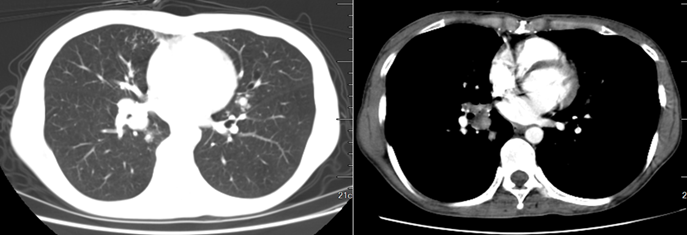

孙武装教授:目前需要进行鉴别诊断。首先,患者咳痰(黄痰)4个月伴咯血,黄痰,提示存在下呼吸道感染,黄痰提示可能为细菌感染。究竟是气道内炎症,还是右肺门病变本身就是炎症,以及是否为混合感染,均有待后续检查确证。其次,右肺门阴影需要进行鉴别。目前检查结果可见CEA升高,通常情况下,CEA升高可能提示腺癌,但右肺门病变多见于鳞癌或小细胞癌,而此种情况CEA一般不会太高。所以从目前的证据分析,我认为肿瘤可以暂时排除。下一步要做强化CT或PET、气管镜检查、EBUS检查等。另外,还需排除淋巴瘤的可能,必要时进行穿刺活检。该患者仍不能除外感染性疾病。检查发现患者有支扩,且倾向于中心型支扩;嗜酸粒细胞升高,但没有过敏性鼻炎,真菌感染的证据缺乏,结核的证据不多,仍需要进一步检查。

治疗后对患者进行了随访。胸部CT对比发现:右肺门结节明显吸收(图6)。